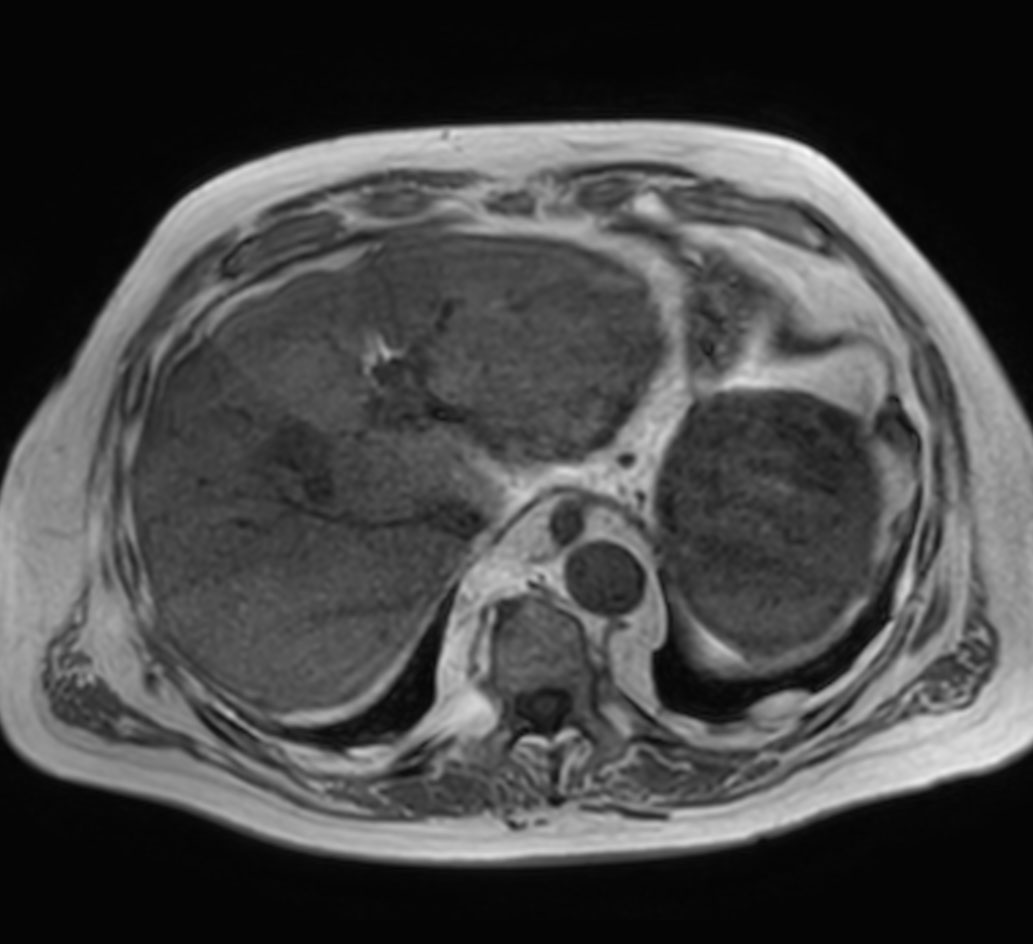

Axial T2w TSE